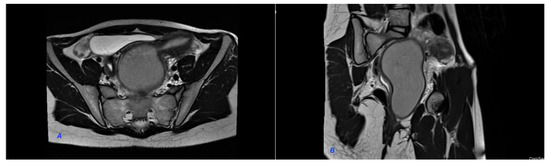

We present a case of HWWS diagnosed in our department in a 16-years-old girl who presented for severe left-lower quadrant pain, nausea, and urinary symptoms. Her menarche started the year before presentation, and monthly bleeding was regular; lasting 4 days; and was accompanied by increasing abdominal pain, nausea, urinary symptoms, and sometimes vomiting. She was not sexually active. During her first gynecology referral from another institution, she was recommended contraceptive pills for severe dysmenorrhea, which she refused. In the first visit in our hospital, the physical examination of the abdomen revealed mild abdominal tenderness of the left lower abdominal quadrant. Abdominal ultrasound (US) was performed but was considered not sufficiently informative; we only observed a voluminous cystic mass corresponding to hematocolpos. Therefore, after a careful explanation of the procedure and counseling, the girl and her parents decided to accept trans-rectal US examination. This revealed a didelphys uterus with a mild hematometra of the left hemiuterus, normal right hemiuterus and an impressive left-side collection, inferior and in connection with the left hemiuterus, corresponding to a hematocolpos. Both ovaries were present and of normal aspect and size (Figure 1). To better describe the findings and in view of the frequent association of congenital anomalies of the reproductive system with renal anomalies, an MRI was recommended and performed. The pelvic MRI showed two clearly separated hemiuteri (didelphys uterus), with mild left hematometra and normal right hemiuterus, mild left hematosalpinx, and an impressive left hemivagina, connected to the left hemiuterus, distended by a content whose signal was similar to methemoglobin, suggesting an obstructed hematocolpos (Figure 2A,B). Blood analysis was within normal range, except CA 125, which measured 89, 62 u/mL (more than the normal range for that age).

Figure 2. MRI of the pelvis. (A). Hematocolpos and left hemiuterus. (B). Hematocolpos and left hemiuterus. The pelvic MRI showed two clearly separated hemiuteri (didelphys uterus), with mild left hematometra and normal right hemiuterus, mild left hematosalpinx and an impressive left hemivagina, connected to the left hemiuterus, distended by a content whose signal was similar to methemoglobin, suggesting an obstructed hematocolpos.